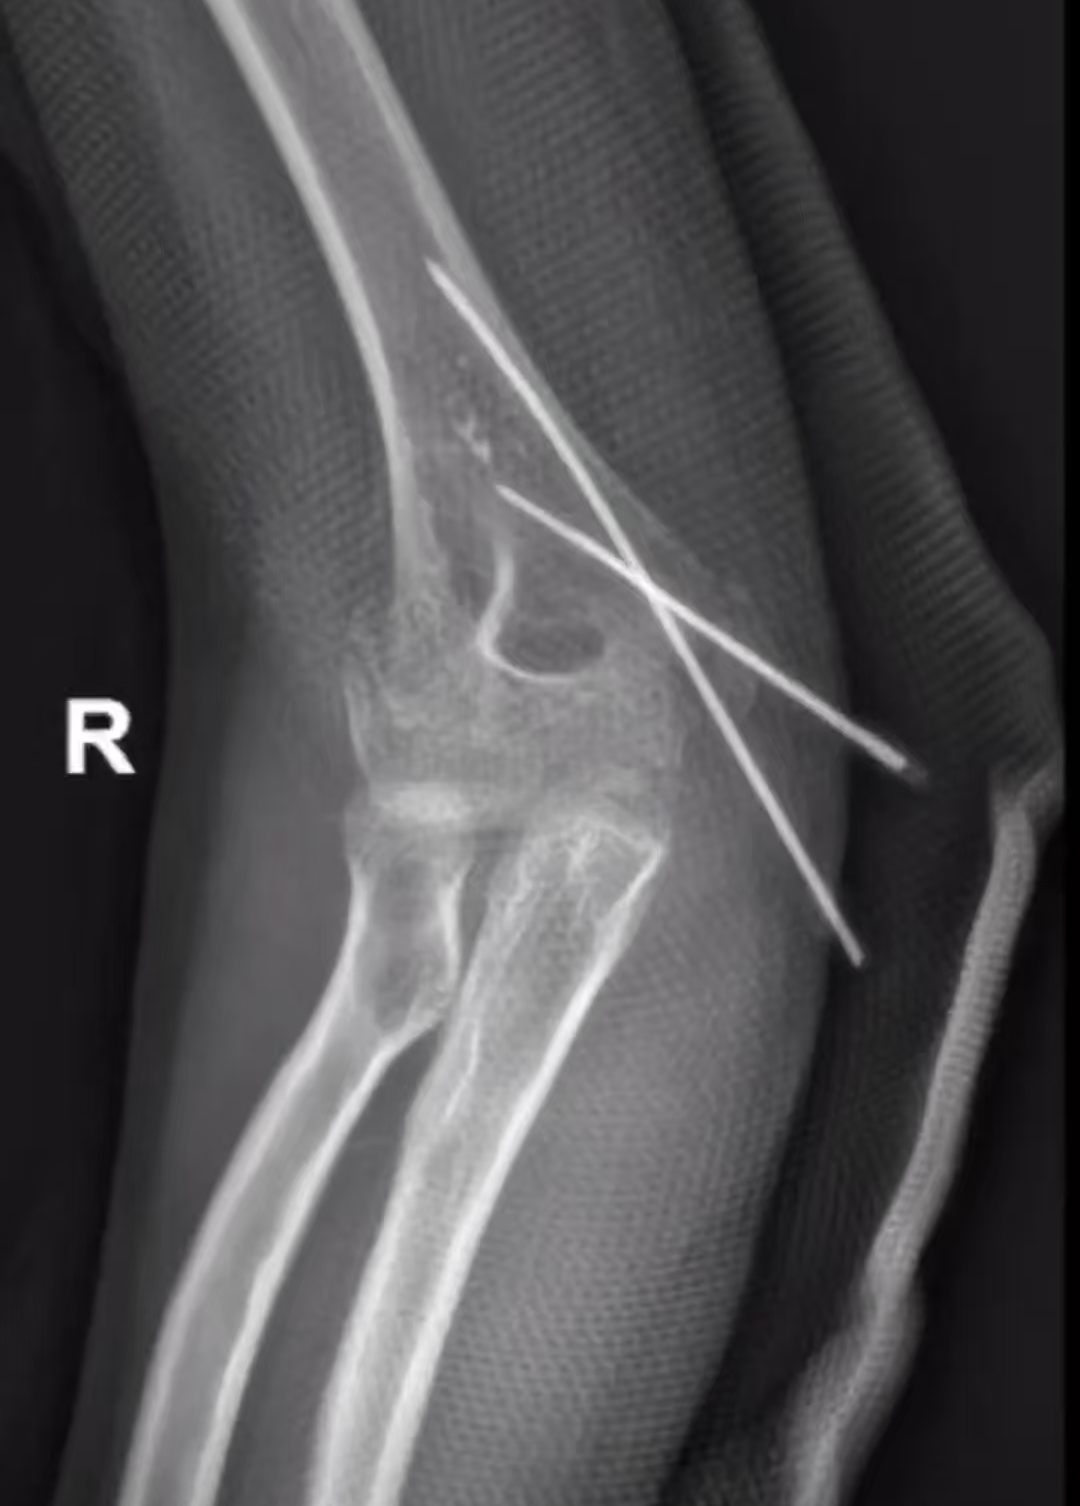

女孩是一名小学学生,平时酷爱网球、乒乓球等挥拍类运动。今年6月份的一天中午午睡时,不慎从床上跌落,右侧肘关节直接着地,当即疼痛难忍。外院就诊后被诊断为“右侧肘关节骨折、右侧肘关节髁间骨折、右侧肘关节关节水肿”,当天下午就进行了右侧肘关节切开骨折复位克氏针固定术。

术后虽然状态良好,但居家制动休息期间,因为克氏针部分外漏,孩子产生了强烈的恐惧心理,自我保护机制让她完全不敢活动右肘关节。据家长描述,居家期间关节活动度最大只能伸肘90度,没有任何主动关节活动和肌肉放松。